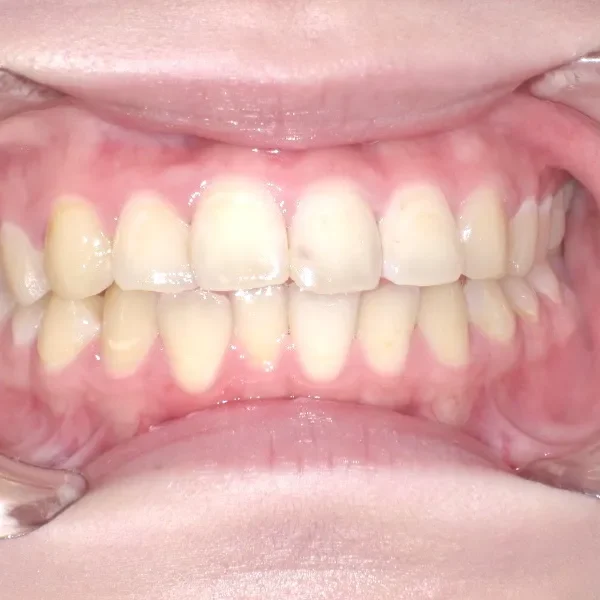

• 治療経過1

治療経過1

再治療の時は、上の歯は前から見えにくいオリジナル固定装置、下の歯はマルチブラケット装置を使用し、治療しました。

治療回数62回、1年6ヶ月の治療期間で矯正治療を終了しました。

前回の治療で歯の根っこの部分の位置を治していたので、全部前から付けるのではなく最低限見える装置で治せました。